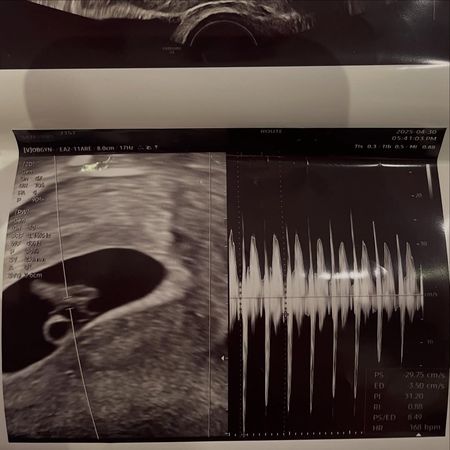

徐敏在於5月2日透過Instagram發文表示:「恭喜你當爸爸了」,並附上一張胎兒的超音波照片,宣告自己懷孕。她同時曬出與疑似孩子生父的男子親密合照,清楚顯示對方長相並公開實名,瞬間引起關注。